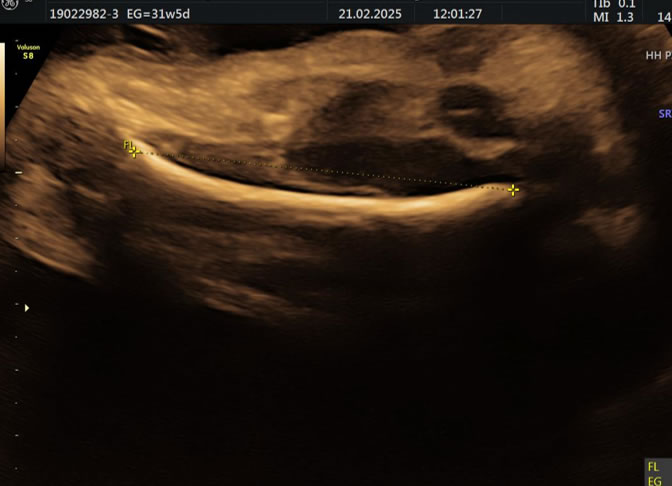

• Eco Doppler III Trimestre